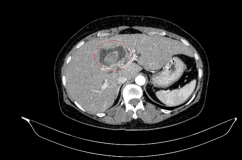

Sidenafil được dùng để điều trị rối loạn cương dương bằng cách làm giãn mạch máu. Khi sử dụng kết hợp với một số loại thuốc theo đơn như nitroglycerin, nó có thể dẫn đến tăng huyết áp gây nguy hiểm. Vì vậy, FDA (Mỹ) mạnh mẽ ra lời kêu gọi mọi người ngừng ngay việc sử dụng loại thuốc này và thiêu hủy toàn bộ lượng thuốc còn lại trên thị trường.